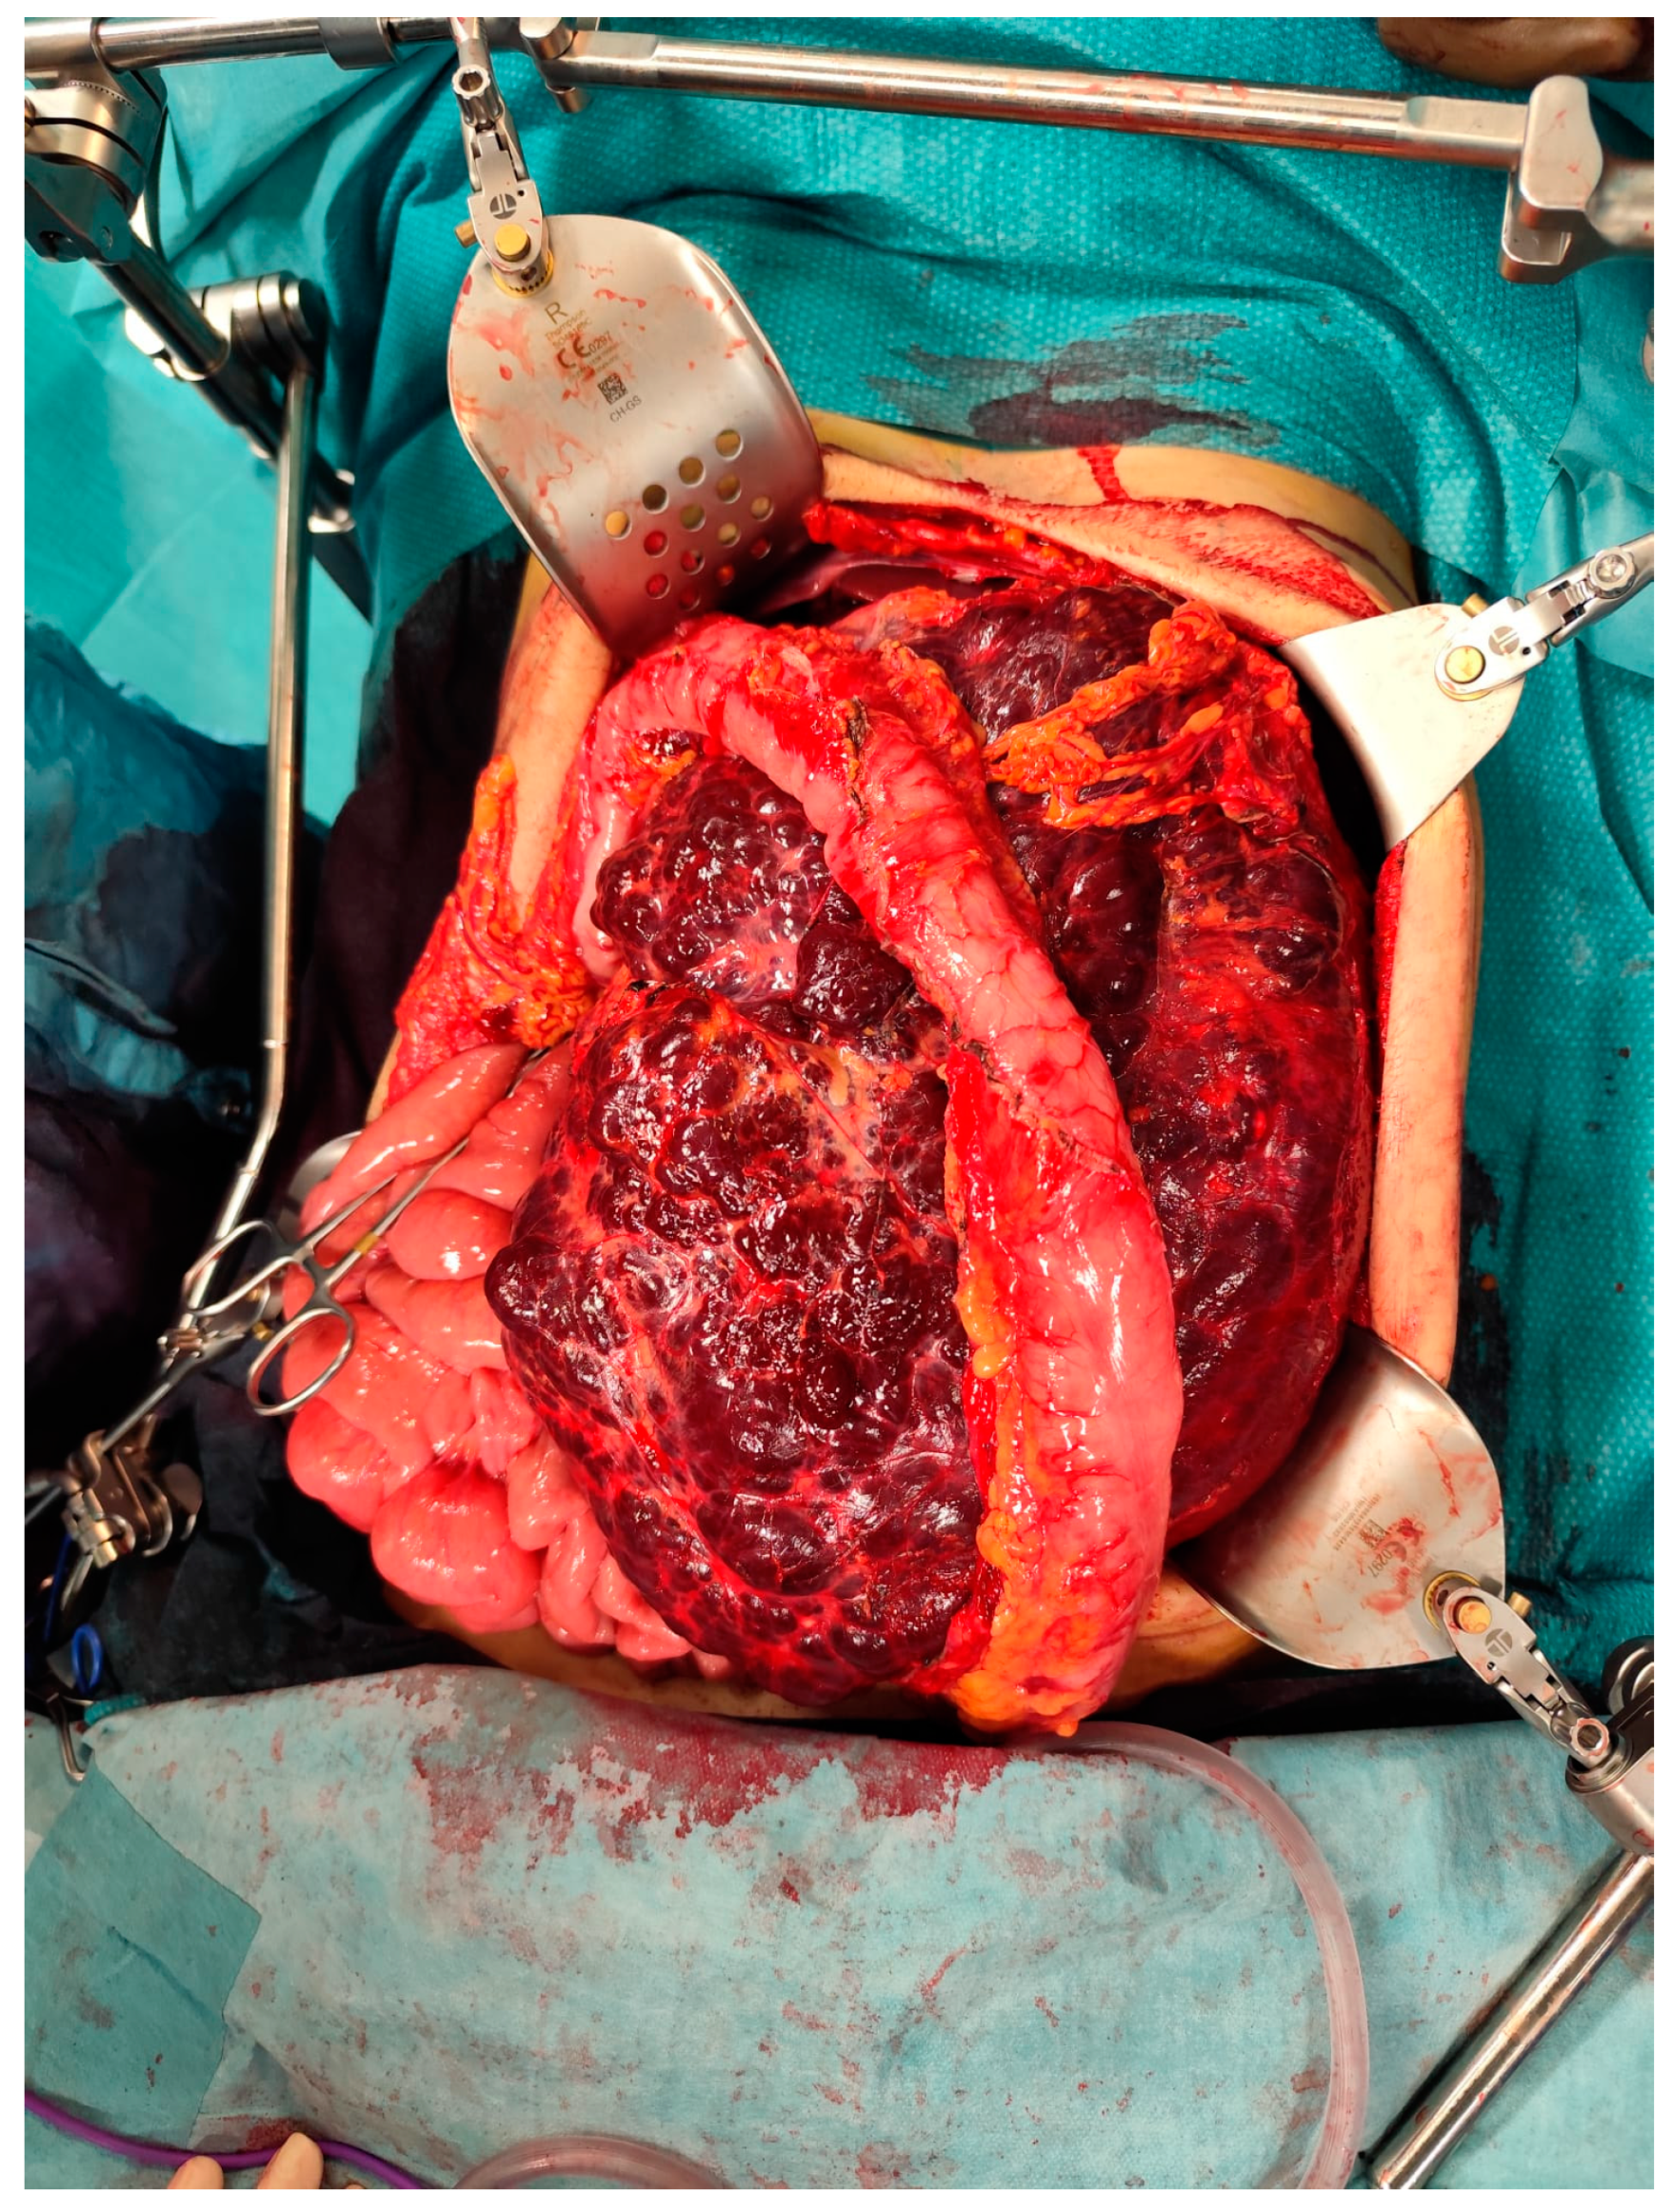

Figure 4. Intraoperative picture showing the mass.

The case was discussed during the dedicated multi-disciplinary meeting and, due to the lesion considerable size and complex structure, as well as the inconclusive results of the biopsy, a surgical resection was advised. The procedure included “en bloc” removal of the left kidney and adrenal gland, both of which were tightly adherent to the mass (Figure 4 and Figure 5).

Postoperative pathological examination revealed a brownish, multiloculated cystic lesion measuring 18 x 17 x 30 cm, with areas of hemorrhage and multiple whitish calcified components. Subsequent analysis identified these calcifications as phleboliths, formed secondary to intralesional thrombotic events.